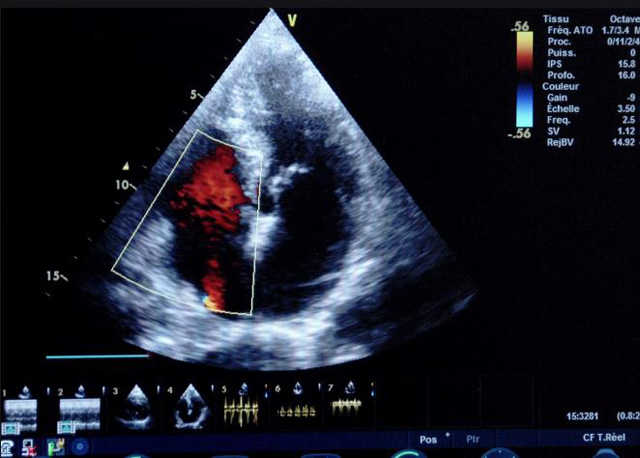

二、彩色室壁運動分析

(一)基本原理彩色室璧運動分析,從整體散射數據中識別心內膜邊界,并與前一幀彩色不同,心臟收縮或舒張期開始到結束時心內膜的全部過程。每一次順序顯示結束后,原來的彩色自動消失,以便進入下一個顯示過程。其結果是獲得對應于每一個心動周期的彩色顯示,描繪特定周期內室壁運動的時間運動軌跡。

(二)操作步驟根據背向散射數據中將心內膜運動的位移過程分類為組織或血液的原理,邊緣檢測跟蹤心內膜和血液的界面。橙色表示收縮期的開始,收縮期不同時相逐幀顯示色彩均疊加在收縮末期最后一幀圖像中。檢查時,可按以下步驟進行:

①顯示較為理想的二維圖像,常用切面有心尖四腔心、二腔心、左心室長軸和左心室乳頭肌水平短軸切面。

②啟動AQ系統,啟動后適當地調節增益補償,顯示心內膜。

③啟動CK系統,啟動后劃定感興趣區域。同時記錄的心動圖R波頂點為舒張末期,T波終點為收縮末期,顯示RT間期的CK彩階圖,連續記錄3~ 5個心動周期。

④對所獲圖像和數據進行分析和計算。

(三)檢測節段性室壁運動異常,研究冠心病患者左心室功能和分析局部室壁運動過程中。測量每一節段室壁的運動量,運動正常的節段彩帶色彩均勻層次光整。運動減弱的節段,厚度薄層次不全。心內膜位移幅度和速度均減低。心內膜位移幅度和速度甚低或難以測得。正常的多層彩帶消失,呈現紅色色帶,心內膜位移呈負向,幅度和速度亦減低。急性心肌梗死的患者中可用于識別存活心肌抑或壞死心肌。多巴酚丁胺負荷試驗存活心肌的心內膜位移幅度增高,停藥后即消失,而壞死心肌則無上述表現。實時檢查冠心病的節段性室壁運動異常,有時候通過發現局部心肌運動的時相異常,對于心臟傳導障礙的診斷也可能有幫助。